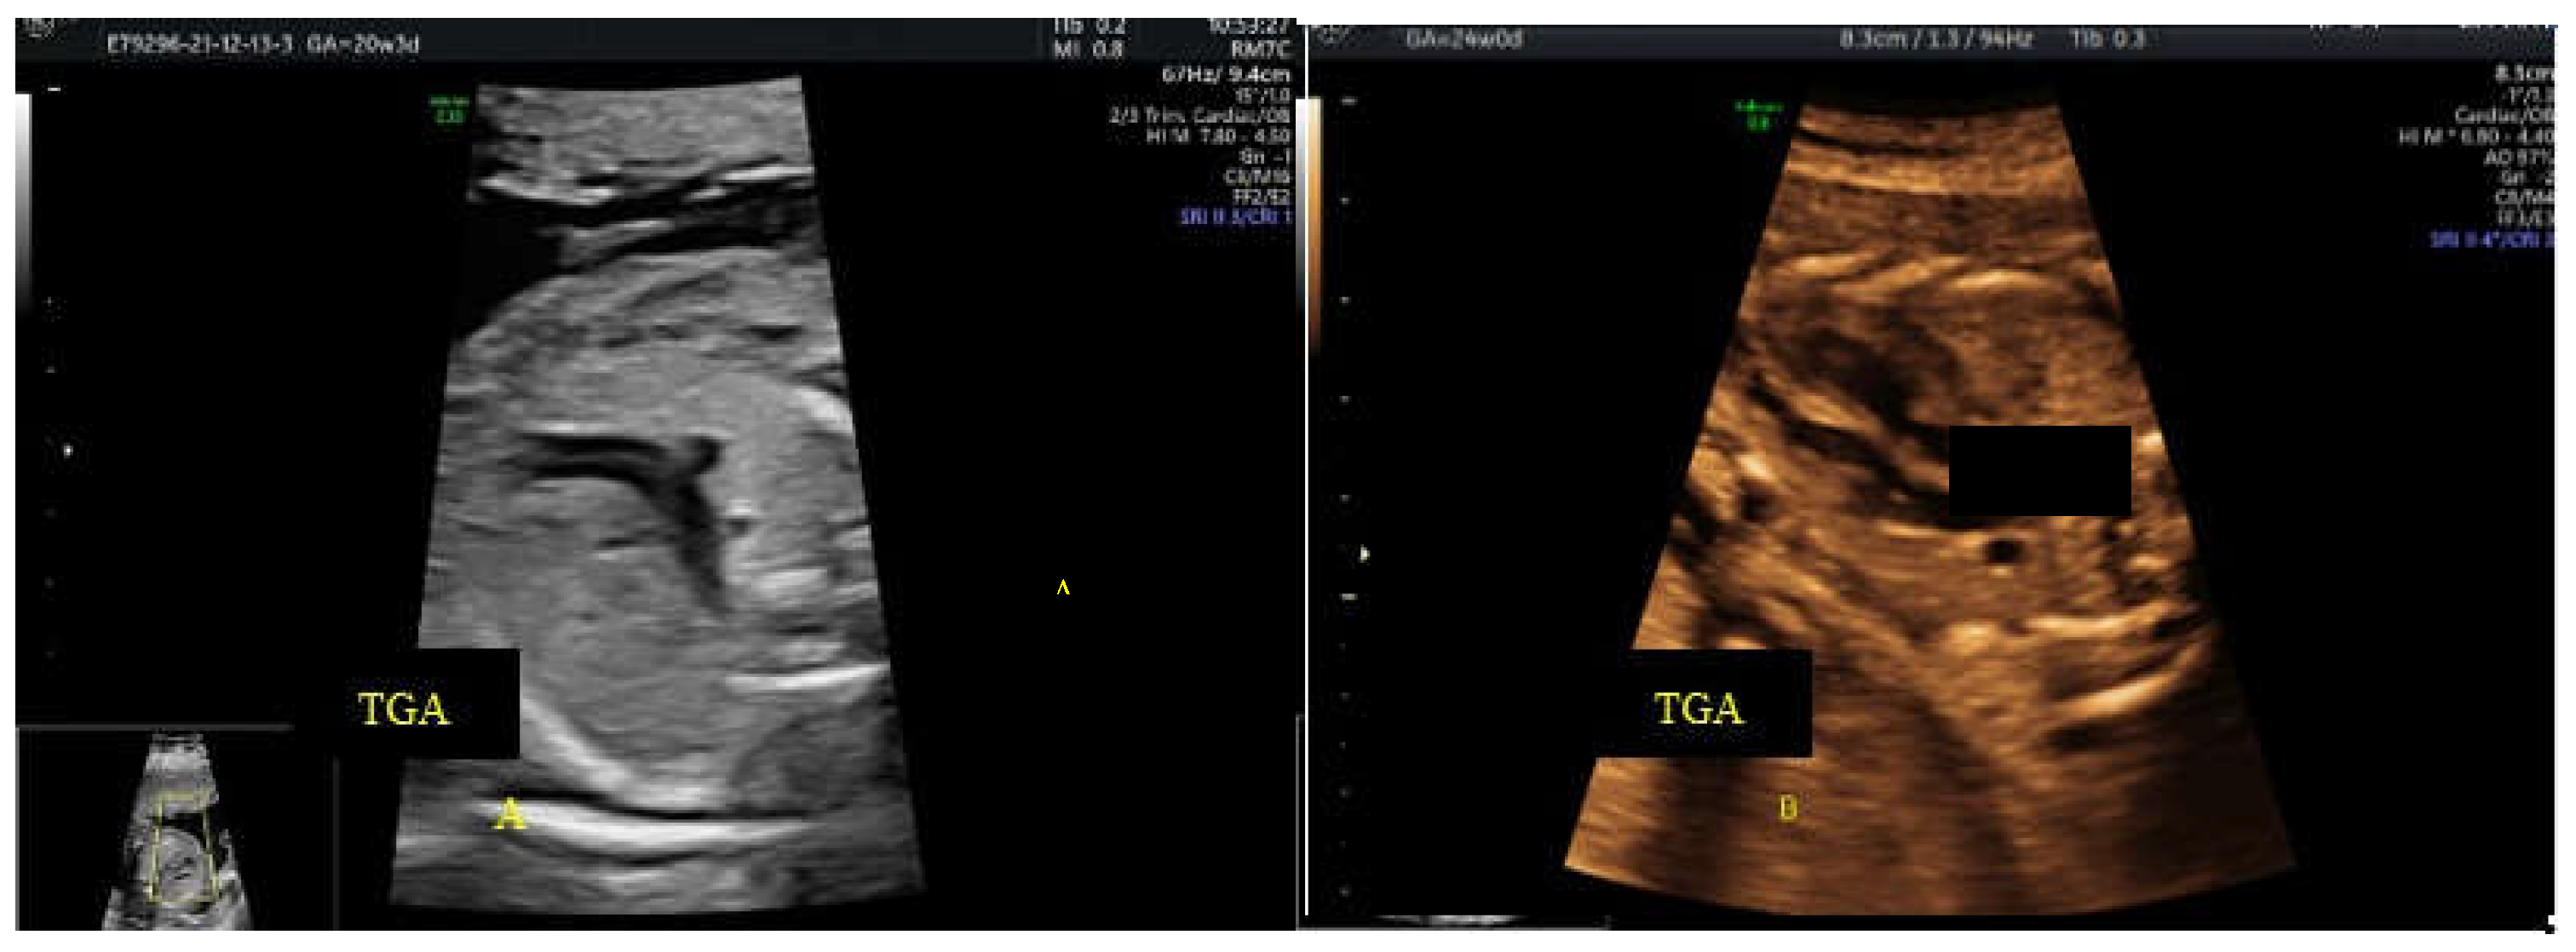

- c. the ”reverse boomerang sign” - the reverse curvature of right ventricle outflow tract (RVOT) at level of the 3VT view in a TGA case